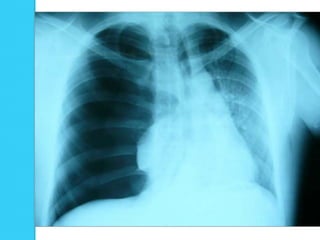

   La existencia de una línea fina, claramente definida, producida por el

margen externo de la pleura visceral, la cual representa el límite del

pulmón, separada de la pleura parietal a nivel de la pared costal por un

espacio lleno de aire, en la proyección AP

   La parte superior de la línea se incurva hacia el ápex pulmonar

   Hiperclaridad, secundaria a un espacio interpleural

   Ausencia de vasos entre el límite del pulmón y la pared torácica

La existencia de una línea fina, claramente definida, producida por el margen externo de la pleura visceral, la cual representa el límite del pulmón, separada de la pleura parietal a nivel de la pared costal por un espacio lleno de aire, en la proyección AP  La parte superior de la línea se incurva hacia el ápex pulmonar  Hiperclaridad, secundaria a un espacio interpleural  Habitualmente existe desplazamiento mediastínico, descenso o aplanamiento de la curva diafragmática ipsilateral y ensanchamiento de los espacios intercostales  Ausencia de vasos entre el límite del pulmón y la pared torácica  En la radiografía en bipedestación se puede observar un menisco cuando existe presencia de una pequeña cantidad de líquido en el espacio pleural

Radiografía en posiciónvertical  El neumotórax se identifica como una delgada línea de pleura visceral rodeada de aire de ambos lados  El tejido pulmonar por dentro de esta línea no tiene aumento de la densidad, a menos que el grado de colapso sea elevado.

Radiografía PA: neumotórax. Se observa la línea pleural (visceral) blanca (flechas) y la ausencia de marcas vasculares pulmonares en la zona lateral a la línea pleural.